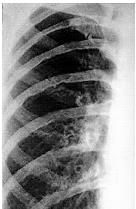

Homem de 25 anos apresenta pressão arterial (PA) variando de 160 × 110 a 170 × 120 mmHg. Chama atenção na sua radiografia de tórax entalhamentos em alguns arcos costais (figura abaixo).

O próximo passo deve ser